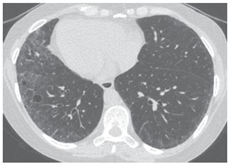

Imagem 3: Histiocitose de células de Langerhans